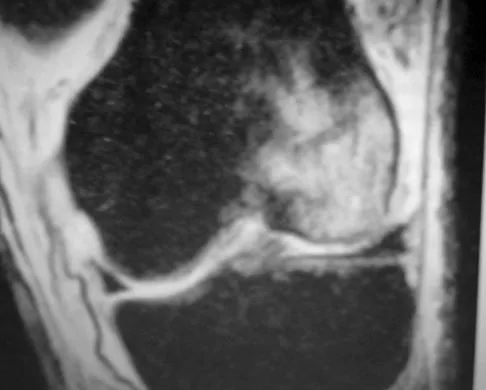

Figure 50 shows the MRI scan of a 20-year-old female college soccer player with knee pain. What is the most likely diagnosis?

Explanation